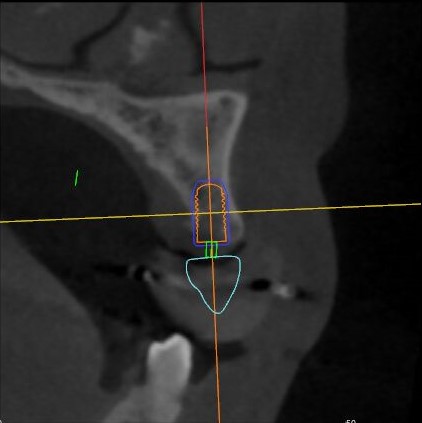

軸狀面視圖

根據(jù)患者CT顯示,使用種植導(dǎo)航軟件設(shè)術(shù)前手術(shù)方案??紤]到患者拒絕手術(shù)摘除上頜竇囊腫等因素,此次手術(shù)選用了Straumann骨水平4.10*8.0mm的植體,植體末端位點(diǎn)設(shè)計(jì)距上頜竇底壁2mm處的同時(shí)兼顧種植方向和修復(fù)間隙,來(lái)達(dá)到理想的效果。

從術(shù)后CBCT顯示可以看出,手術(shù)操作中完美地避開(kāi)上頜竇底,并兼顧了正確的種植方向和修復(fù)間隙